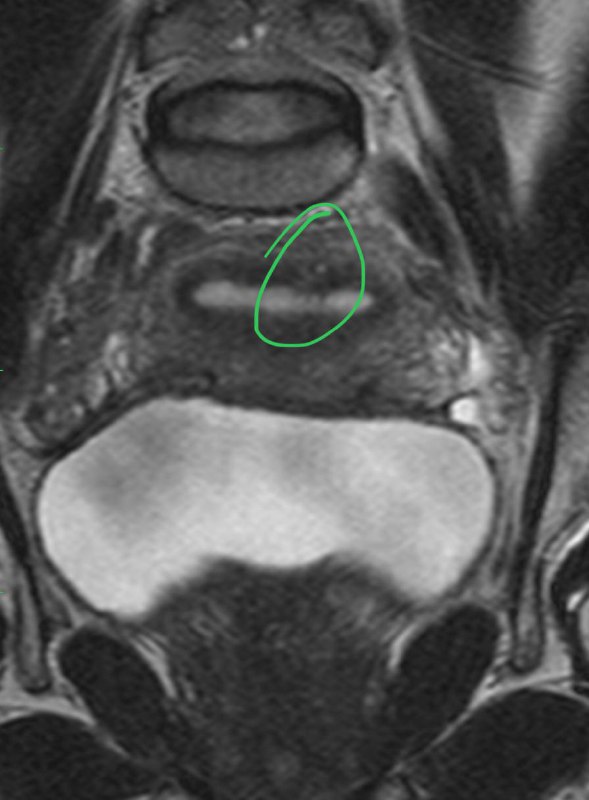

Мелкий фокус аденомиоза.

Субэпендимальные узелки при туберозном склерозе у плода.

Свободные костно-хрящевые внутрисуставные тела в коленном суставе.

Разрыв передней крестообразной связки. Угол между ней и крышей межмыщелковой ямки открыт не вперед, а назад.

Мелкая липома четверохолмной цистерны.

Микроаденома гипофиза, которая видна только в раннюю постконтрастную фазу на динамическом сканировании.

Частичный разрыв передней малоберцово-таранной связки.